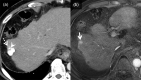

MRI is widely used in clinical practice for detecting liver diseases. Since the introduction of gadoxetic acid, MRI has become the most effective modality for the detection and characterization of focal liver lesions. According to previous meta-analyses, the area under the receiver operating characteristic curve (AUROC) was 0.97-0.99 for the diagnosis of small hepatocellular carcinoma (≥ 2 cm) by gadoxetic-acid-enhanced MRI. Moreover, the AUROC for the diagnosis of colorectal liver metastases was significantly high (0.98). Despite gadoxetic acid's drawbacks, its clinical utility outweighs them, making it the contrast agent of choice in routine liver MRIs. Moreover, clinically, liver MRI has become more prevalent for a quantitative assessment. Liver fibrosis can be evaluated using MR elastography; whereas, hepatic steatosis and iron overload can be evaluated using proton density fat fraction, with high accuracy and reproducibility. This article reviewed the usefulness of liver MRI, which can be a comprehensive imaging modality in clinical practice.